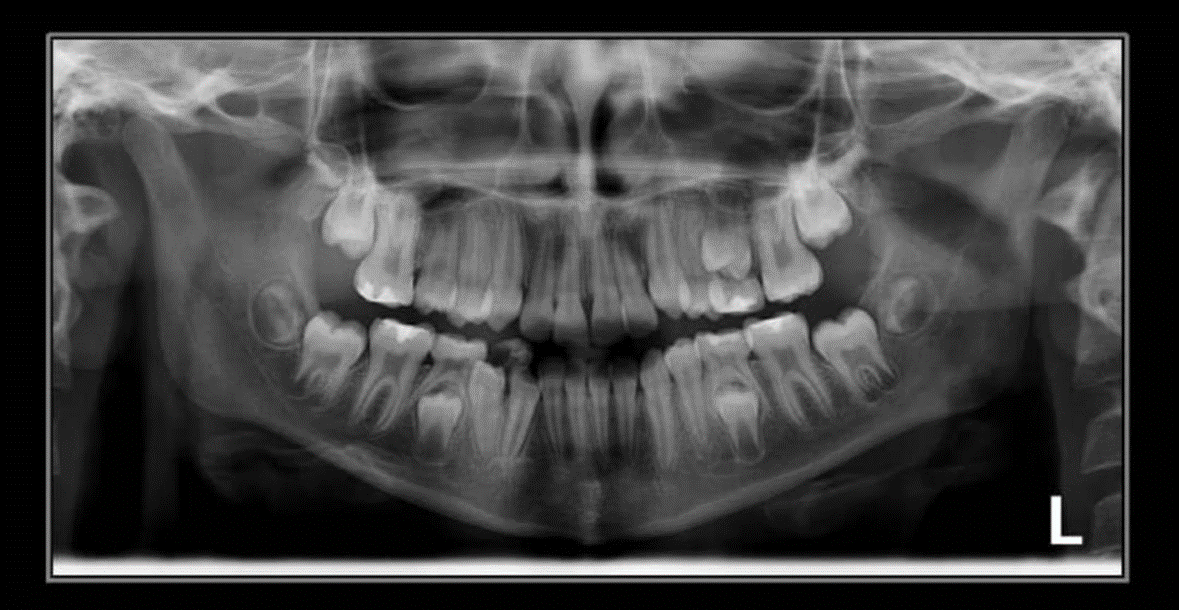

2. How old is the patient with the following X ray?